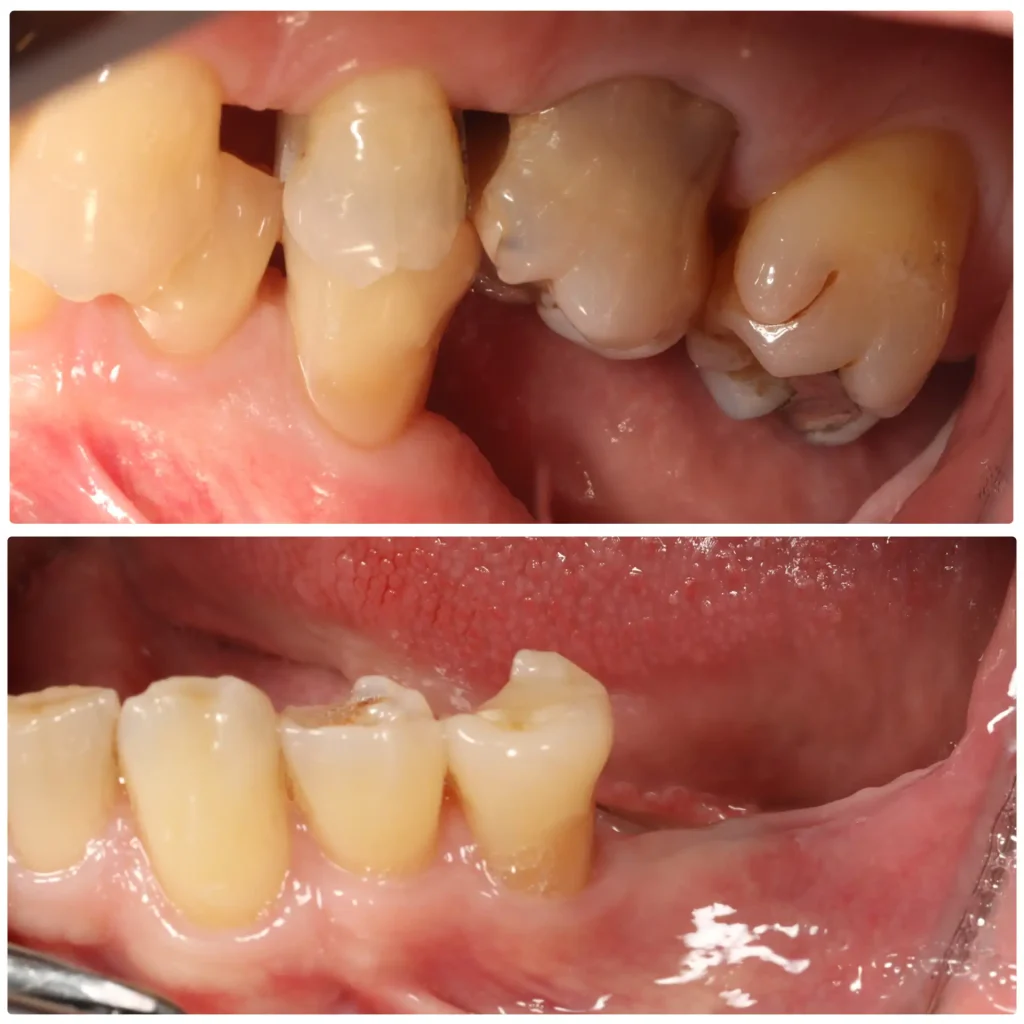

Case studies